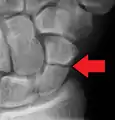

A more obvious scaphoid fracture on a scaphoid view X ray